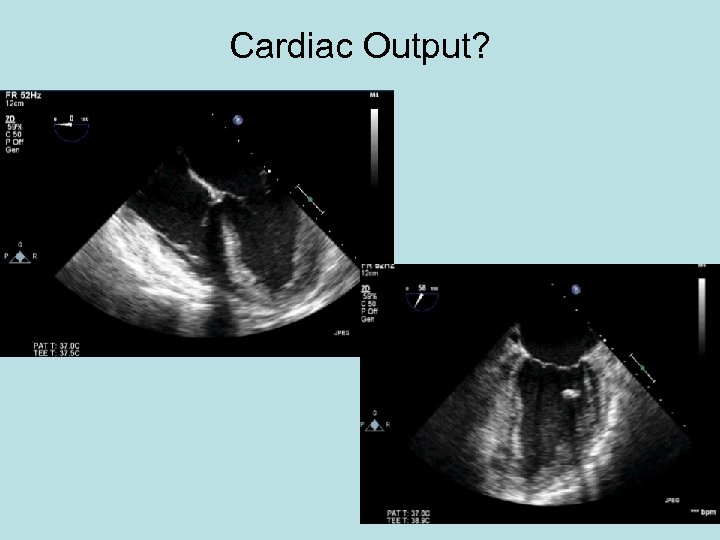

Cardiac Output?

Volume. Clue bottom left